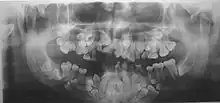

Panoramic view of the jaws showing multiple unerupted supernumerary teeth mimicking premolar, missing gonial angles and underdeveloped maxillary sinuses in cleidocranial dysplasia.